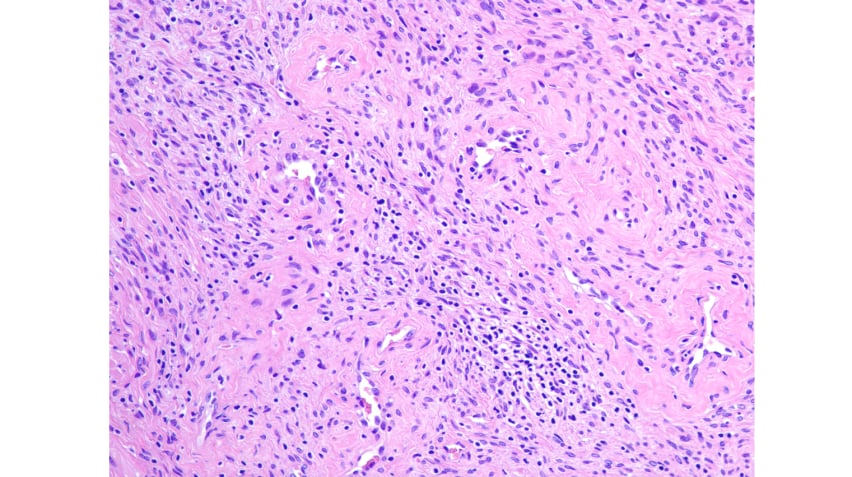

间质梭形细胞弥漫性过度增生,中度丰富,排列紊乱,异型性明显

可见良性腺体陷入增生的梭形细胞中

核增大,深染,未见明显核仁,见明显的核分裂象

诊断思路:病理诊断需遵循严谨的逻辑。对于梭形细胞病变,需自问:细胞是否有胶原产物?病变是否为肿瘤?肿瘤是否恶性?是否为肉瘤?肉瘤来源何处?本病例显示明显的细胞异型性及病理性核分裂象,提示恶性。